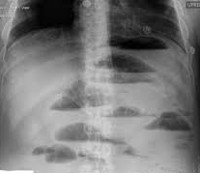

• Рентгенографическое исследование. При панорамном рентгенологическом исследовании брюшной полости, выполненном в положении лежа на спине, видны обширные кишечные петли с присутствием жидкости. На рентгенограмме в вертикальном положении с обструкцией тонкой кишки, чаши Клойбера (опухший кишечный отек с горизонтальным уровнем жидкости), выявляются складки Керкринга.